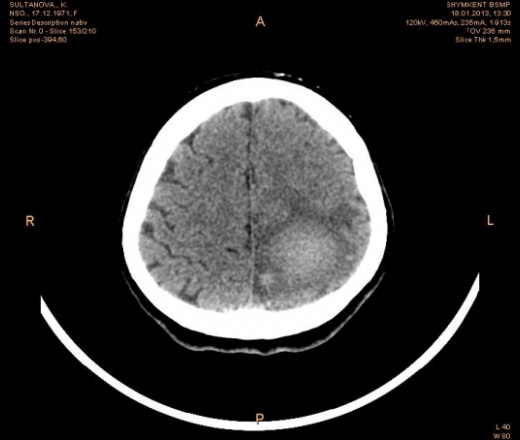

АВМ в затылочной доле, дренаж через большую вену мозга и межполушарные вены.

Красная стрелка дренаж в большую вену мозга. Голубая ррасширенная вена в межполушарной щели. Наверное есть и еще, но не все показано. Клубок расширенных, "неправильных" сосудов в левой затылочной доле, я думаю, хорошо виден.

Предположу, что синей стрелкой указана питающая АВМ левая передняя мозговая артерия

Верно. Только отток из ГМ преимущественно осуществляется через дорсально расположенные вены и синусы.